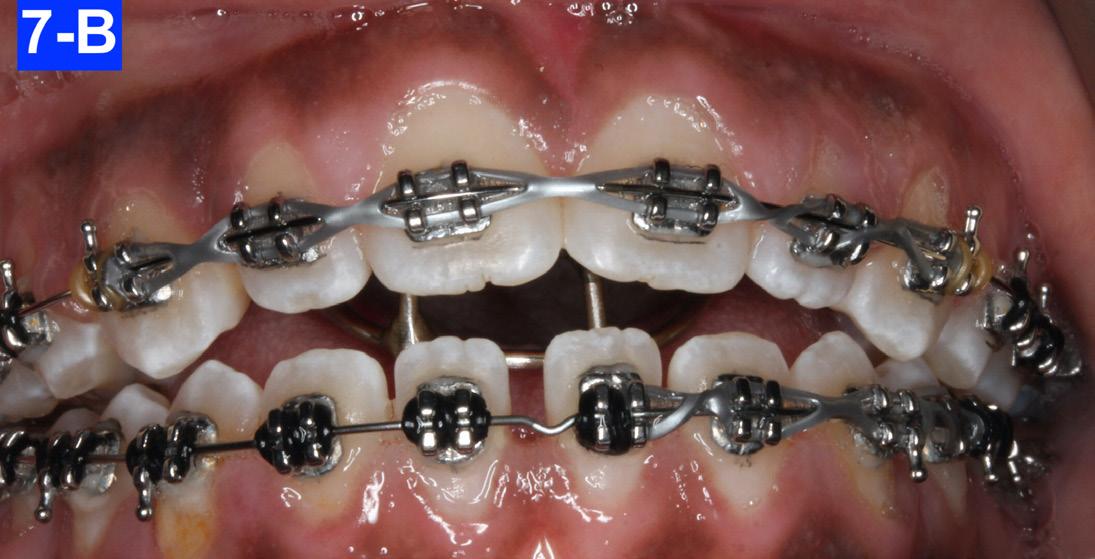

The following appointment, we placed a .018 SS in the maxilla and a .018 NiTi in the mandible. An EC was placed from #13(6) to #23(11), and in the mandible from #43(27) to 34(21) to close the spaces (Figure 7-A, B. C).

Fig. 7-C: MX a. 018 SS, MN a .019 NiTi

Fig. 7-A: Maxilla, a .016 NiTi

Fig. 7-B: MX a .018 NiTi, MN a .016 NiTi